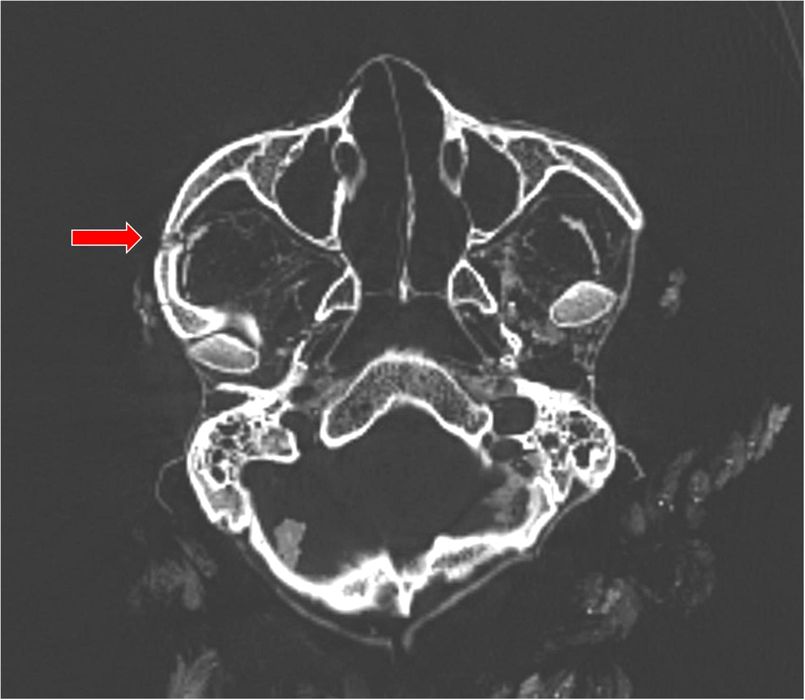

Trei mumii din America de Sud au fost ucise cu brutalitate, arată tomografiile

Unul dintre secretele trecutului care poate fi dezvăluit prin studiul craniilor și scheletelor este cât de frecventă a fost violența printre strămoșii noștri. Ce spun tomografiile despre 3 mumii din America de Sud? O analiza […]